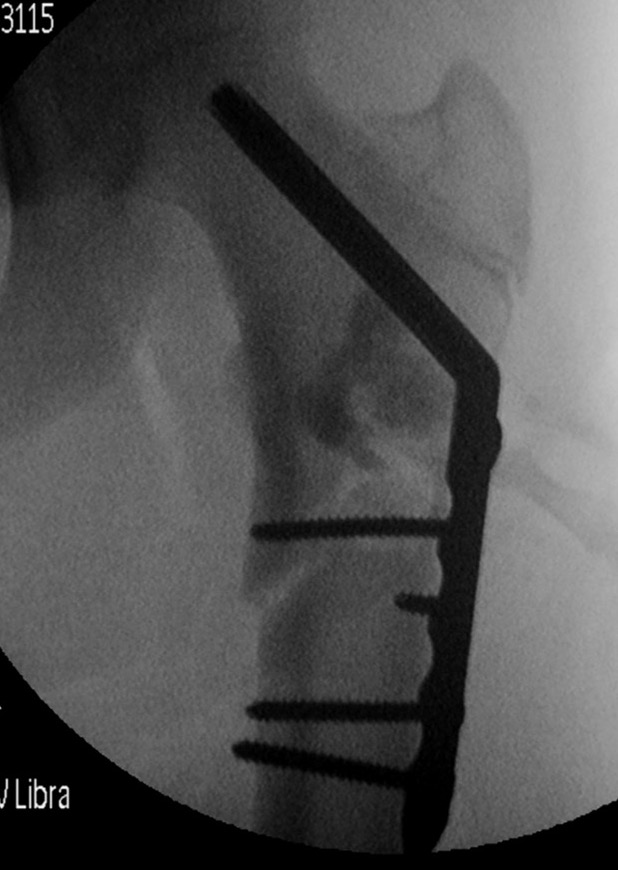

Surgical cyst drainage using implants

Concept

- venous hypertension cause of cyst

- if allow cyst to drain, will heal

Options

- cannulated screws in calcaneum

- flexible nails humerus

- intramedullary nail femur

Results

Erol et al J Paediatr Orthop B 2017

- humeral simple bone cysts

- 37 curettage and bone graft

- 16 had addition of flexible nails

- 76% healing curettage and bone graft

- 100% healing with flexible nails